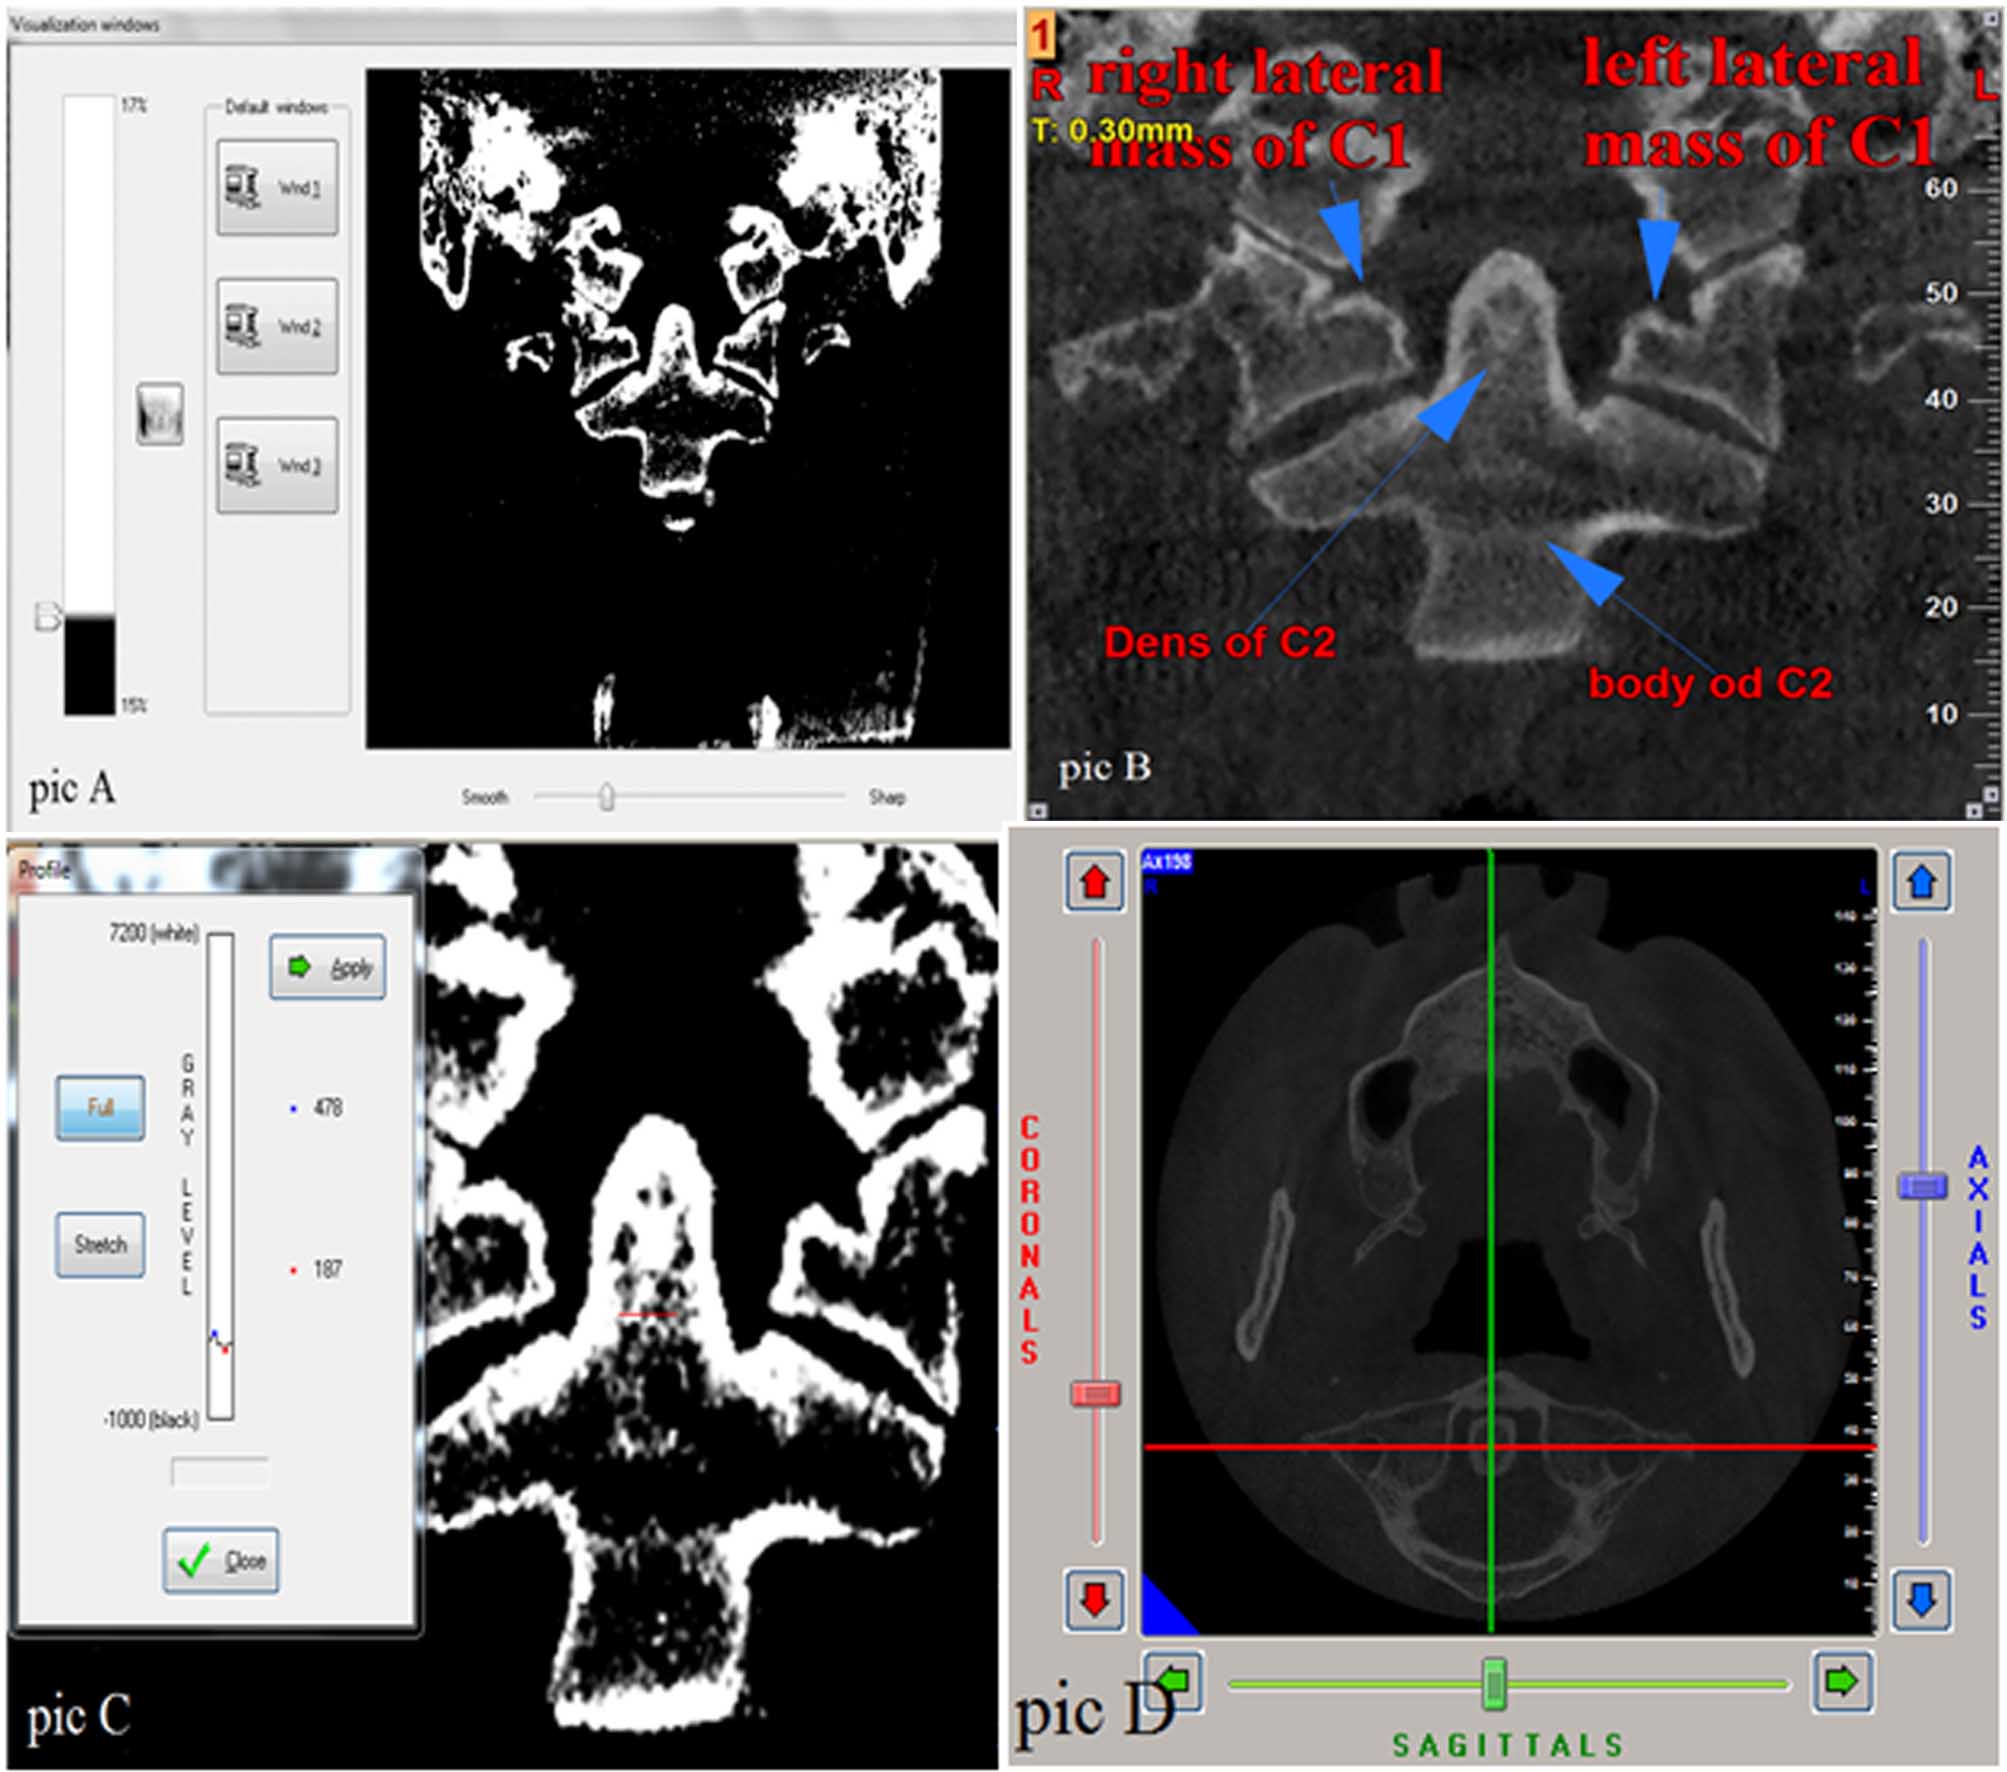

These steps lead to the creation of a homogenous density between different scans and enhancement of credibility of the present study. RD values were recorded in window width of 17% and window level of 15%, which make the images white and black. Also the sharpness was adjusted to provide an approximately smooth image (Figure 1-A). Then the RD values were recorded in four areas, including lateral mass of C1 on the both the right and left sides and the dens and body of C2 by using NNT Viewer software (Figure 1-B, C). The coronal section which passes through the middle of the dens (Figure 1-D) was selected and evaluated under a magnification of %175. RD values were recorded in five sites of these areas; four of the sites were in the margins and one of them was in the center of the areas. Then, the average of RD values was calculated and this number was considered as the area’s main RD value.

Figure 1. A, Adjusting the window width, window level and sharpness of the images. B, Areas under review. C, Measuring RD values in dens. D, The coronal section passes through the middle of the dens.